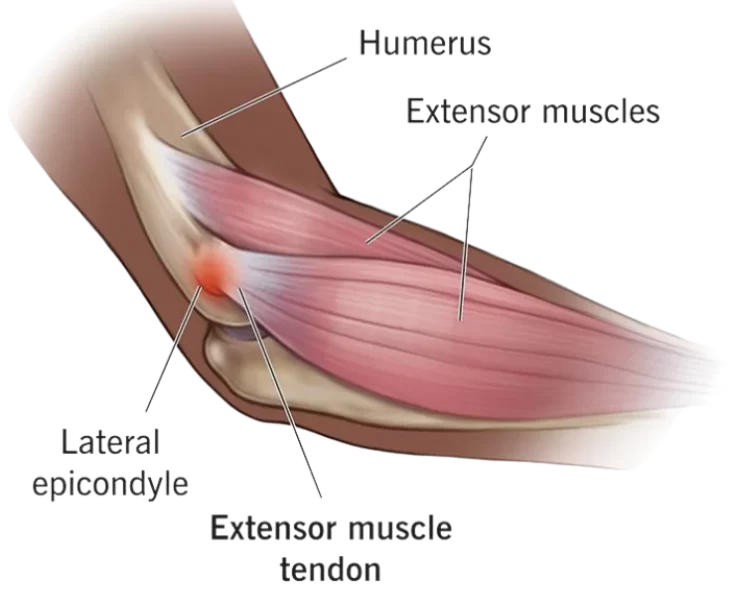

PRP Injection for Tennis Elbow

PRP therapy is a “non-surgical” technique performed in the clinic that begins with the collection of a little sample of your own blood.

Tennis Elbow Release

Lateral epicondylitis release is a surgical treatment that is performed to alleviate the symptoms of lateral epicondylitis, also known as tennis elbow.